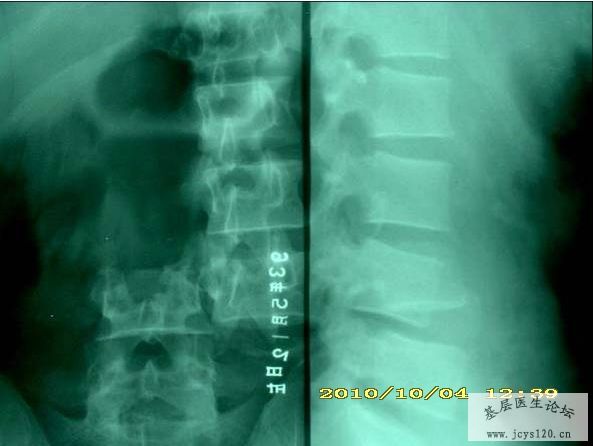

同行帮给看一下这个造影,需要怎么治疗比较理想